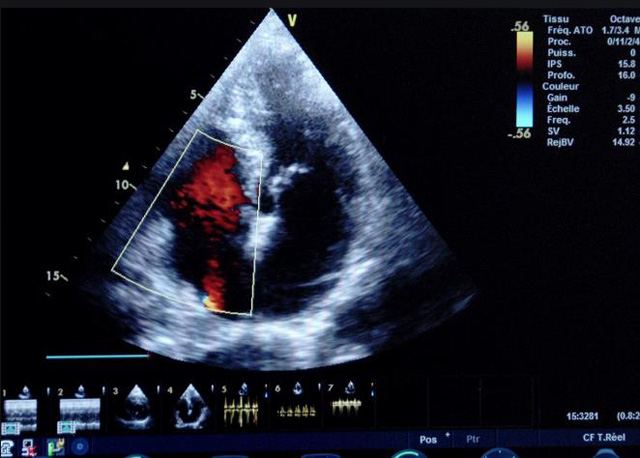

二、彩色室壁運(yùn)動(dòng)分析

(一)基本原理彩色室璧運(yùn)動(dòng)分析,從整體散射數(shù)據(jù)中識(shí)別心內(nèi)膜邊界,并與前一幀彩色不同,心臟收縮或舒張期開(kāi)始到結(jié)束時(shí)心內(nèi)膜的全部過(guò)程。每一次順序顯示結(jié)束后,原來(lái)的彩色自動(dòng)消失,以便進(jìn)入下一個(gè)顯示過(guò)程。其結(jié)果是獲得對(duì)應(yīng)于每一個(gè)心動(dòng)周期的彩色顯示,描繪特定周期內(nèi)室壁運(yùn)動(dòng)的時(shí)間運(yùn)動(dòng)軌跡。

(二)操作步驟根據(jù)背向散射數(shù)據(jù)中將心內(nèi)膜運(yùn)動(dòng)的位移過(guò)程分類(lèi)為組織或血液的原理,邊緣檢測(cè)跟蹤心內(nèi)膜和血液的界面。橙色表示收縮期的開(kāi)始,收縮期不同時(shí)相逐幀顯示色彩均疊加在收縮末期最后一幀圖像中。檢查時(shí),可按以下步驟進(jìn)行:

①顯示較為理想的二維圖像,常用切面有心尖四腔心、二腔心、左心室長(zhǎng)軸和左心室乳頭肌水平短軸切面。

②啟動(dòng)AQ系統(tǒng),啟動(dòng)后適當(dāng)?shù)卣{(diào)節(jié)增益補(bǔ)償,顯示心內(nèi)膜。

③啟動(dòng)CK系統(tǒng),啟動(dòng)后劃定感興趣區(qū)域。同時(shí)記錄的心動(dòng)圖R波頂點(diǎn)為舒張末期,T波終點(diǎn)為收縮末期,顯示RT間期的CK彩階圖,連續(xù)記錄3~ 5個(gè)心動(dòng)周期。

④對(duì)所獲圖像和數(shù)據(jù)進(jìn)行分析和計(jì)算。

(三)檢測(cè)節(jié)段性室壁運(yùn)動(dòng)異常,研究冠心病患者左心室功能和分析局部室壁運(yùn)動(dòng)過(guò)程中。測(cè)量每一節(jié)段室壁的運(yùn)動(dòng)量,運(yùn)動(dòng)正常的節(jié)段彩帶色彩均勻?qū)哟喂庹?。運(yùn)動(dòng)減弱的節(jié)段,厚度薄層次不全。心內(nèi)膜位移幅度和速度均減低。心內(nèi)膜位移幅度和速度甚低或難以測(cè)得。正常的多層彩帶消失,呈現(xiàn)紅色色帶,心內(nèi)膜位移呈負(fù)向,幅度和速度亦減低。急性心肌梗死的患者中可用于識(shí)別存活心肌抑或壞死心肌。多巴酚丁胺負(fù)荷試驗(yàn)存活心肌的心內(nèi)膜位移幅度增高,停藥后即消失,而壞死心肌則無(wú)上述表現(xiàn)。實(shí)時(shí)檢查冠心病的節(jié)段性室壁運(yùn)動(dòng)異常,有時(shí)候通過(guò)發(fā)現(xiàn)局部心肌運(yùn)動(dòng)的時(shí)相異常,對(duì)于心臟傳導(dǎo)障礙的診斷也可能有幫助。